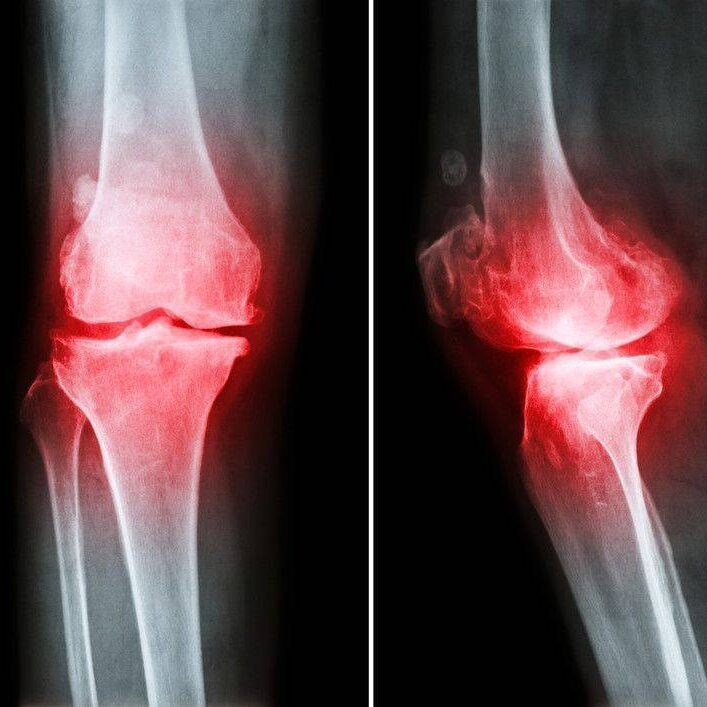

Bel ve boyun fıtığı, diz ve omuz ağrıları, menisküs problemleri, eklem kireçlenmeleri ve ameliyat sonrası rehabilitasyon süreçleri klinik ortamda profesyonel şekilde yürütülür. Ortopedik sorunların tedavisinde manuel terapi teknikleri, egzersiz uygulamaları ve fonksiyonel hareket eğitimleri bir arada kullanılır.